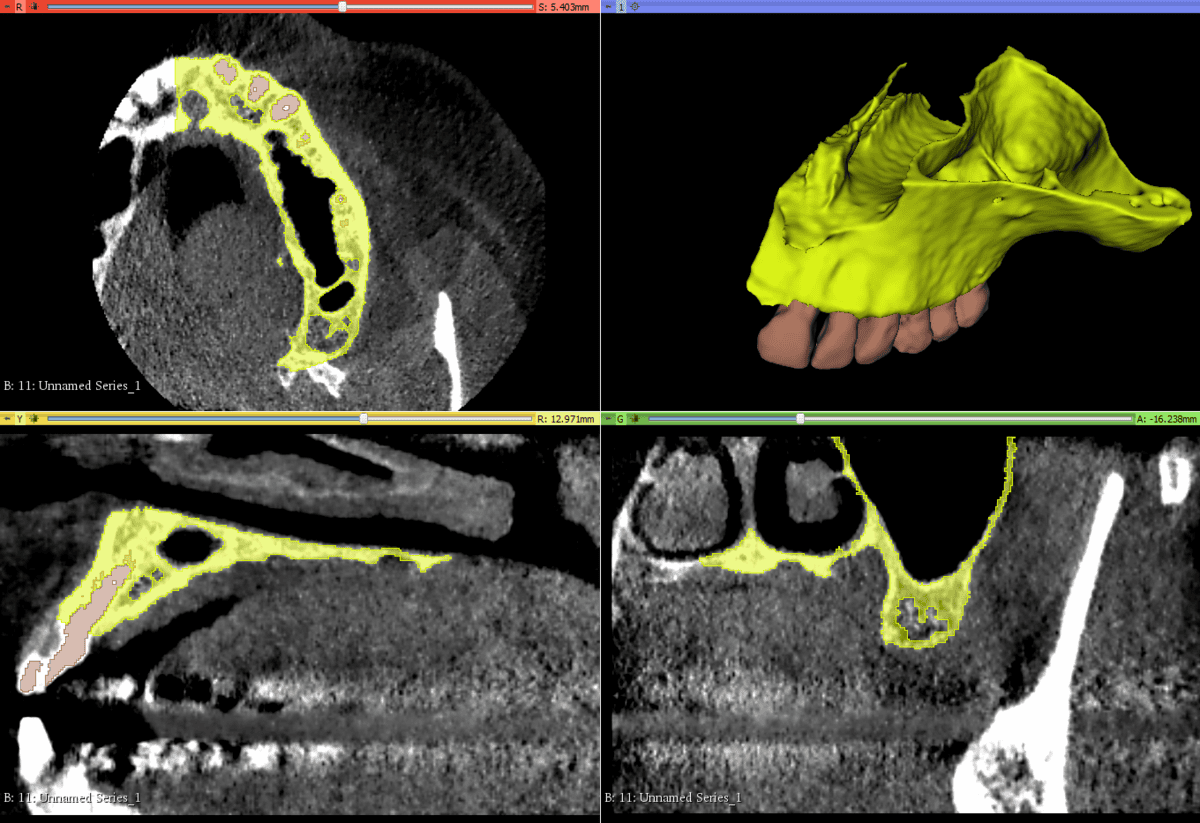

CBCT and Segmentation

Data from the CBCT are carefully segmented into the different tissue

Tissue definition

Bone, teeth, soft tissue, Schneiderian membrane are defined and represented

Anatomic representation

Precise anatomic reproduction of the actual surgical anatomy is designed

A Challenging surgical case with a complex of vertical and horizontal septa in the posterior sinus. Segmentation of the 3D radiographical and optical data and 3D printing in multiple layers from AMMA Ltd Hong Kong, has allowed for an accurate representation of the anatomy where multiple surgical access approaches were tested.